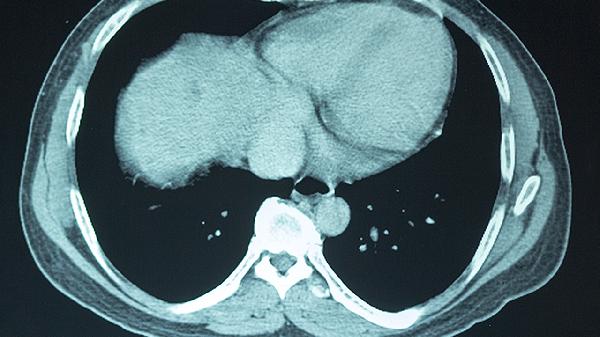

頭部CT或核磁共振可排除顱內(nèi)出血、顱骨骨折等器質(zhì)性損傷。雖然腦震蕩通常無結(jié)構(gòu)性改變,但影像學(xué)能鑒別更嚴(yán)重的創(chuàng)傷性腦損傷。對于持續(xù)頭痛或嘔吐的患者,建議完善影像學(xué)評估。